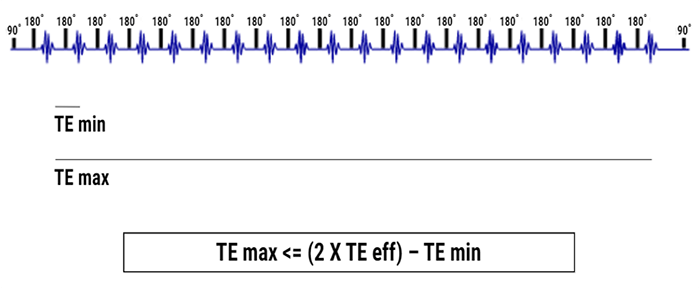

When the difference between the weight of the echo that fills the center and the echoes that fill the periphery is too large, this blurring artifact appears. In an optimum setting, the Max TE should not be more than double the TE eff minus the TE min.

Optimizing the Effect:

To reduce the blurring artifact, the effective TE must be in the center of the echo train. Based on the manufacturers, the parameters are more or less automated. Some systems automatically alter the values of inter-echo space so that Max TE is double the Effective TE. Some allow full control, which implies a knowledge of this problem. Some others still leave some room for maneuver or adjustment to parameters.

Next, we will develop the rationale for a system that doesn’t have any automatic mechanism in order to properly identify the different aspects of managing these parameters